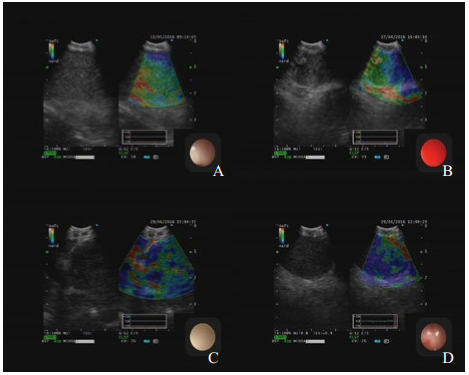

| A淋巴结回声中等,边界不清,回声均,大小23.4 mm×20.3 mm,弹性评分1分,EBUS-TBNA病理示结核;B淋巴结回声中等,边界不清,回声不均,大小16.9 mm×25.6 mm,弹性评分2分,EBUS-TBNA病理示结节病,C淋巴结低回声,边界清,回声不均,大小27 mm×36.4 mm,弹性评分3分,EBUS-TBNA病理示腺癌,D淋巴结低回声,边界清,回声均,大小32 mm×37.7 mm,弹性评分4分,EBUS-TBNA病理示小细胞肺癌 图 1 典型淋巴结常规超声及USE图像 |

通过软件收集弹性成像图片(JPEG图像),使用image-J软件计算出蓝色区域占淋巴结区域比值,进行弹性成像评分。评分标准[12]:①1分:小于20%的切面显示为蓝色;②2分:20%~50%的切面显示蓝色;③3分:50%~80%的切面显示为蓝色;④4分:超过80%的切面显示为蓝色。见图 1。